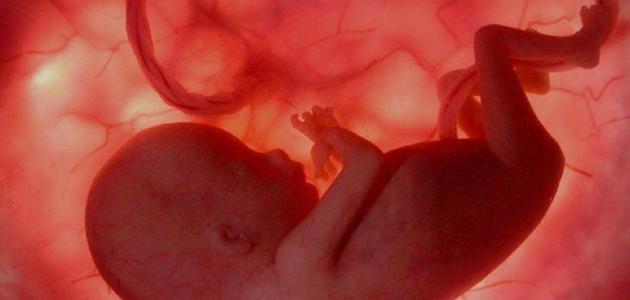

شكل الجنين في الشهر الرابع

في بداية الأسبوع الرابع عشر

- يبدأ الجنين بالحركة في الرحم، إلّا أنّ الشعور به يكاد يكون منعدماً.

- يصل طوله إلى 10 سم، ووزنه إلى 50-55 غراماً.

- تتكوّن أسنانه تحت اللثة بالتزامن مع نموّ الشعر والجسم في الوقت ذاته.

- تصبح عظامه أكثر قوّة.

- يكون مغمضاً لعينيه، كما يبتسم في بعض الأحيان.

في الأسبوع الخامس عشر

- يكتمل نموّ أعضائه ومظهره الخارجيّ بشكل كبير.

- يصل طوله إلى 10-15 سم، ووزنه إلى 50-70 غراماً.

- تصبح الأعضاء الجنسيّة أكثر وضوحاً، بحيث يتم تمييز جنس الجنين ذكراً أم أنثى.

- تصبح الكليتان جاهزتين للقيام بوظيفتهما رغم عدم نضجهما تماماً، إلا أنّ المحيط الذي يوجد فيه الجنين يمنعهما من العمل.

في الأسبوع السادس عشر

- يكتمل نمو الأجزاء الصغيرة في جسمه أو تكون في مراحلها النهائيّة.

- تبدأ الغدّة الدرقية بالعمل، وهي المسؤولة عن إفراز الهرمونات المساعدة للجسم على القيام بعمليّة الأيض بالشكل الصحيح.

- يزداد نشاطه وحركته في بطن الأم، مع إمكانيّة الإحساس بحركته من يوم لآخر.

- يكتمل نموّ أظافره في الأطراف.

في الأسبوع السابع عشر

- يصبح طول الجنين أكثر من 15 سم بقليل، ووزنه أكثر من 120 غراماً.

- يقترب الجهاز العصبيّ من الاكتمال.

- تبدأ غالبيّة الأجهزة في جسمه بالعمل، مثل: عضلة القلب والجهاز التناسليّ.

- تصل المثانة إلى أقصى نشاطها؛ بحيث تدرّ البول كلّ خمس وأربعين دقيقة تقريباً في سائل السلي.